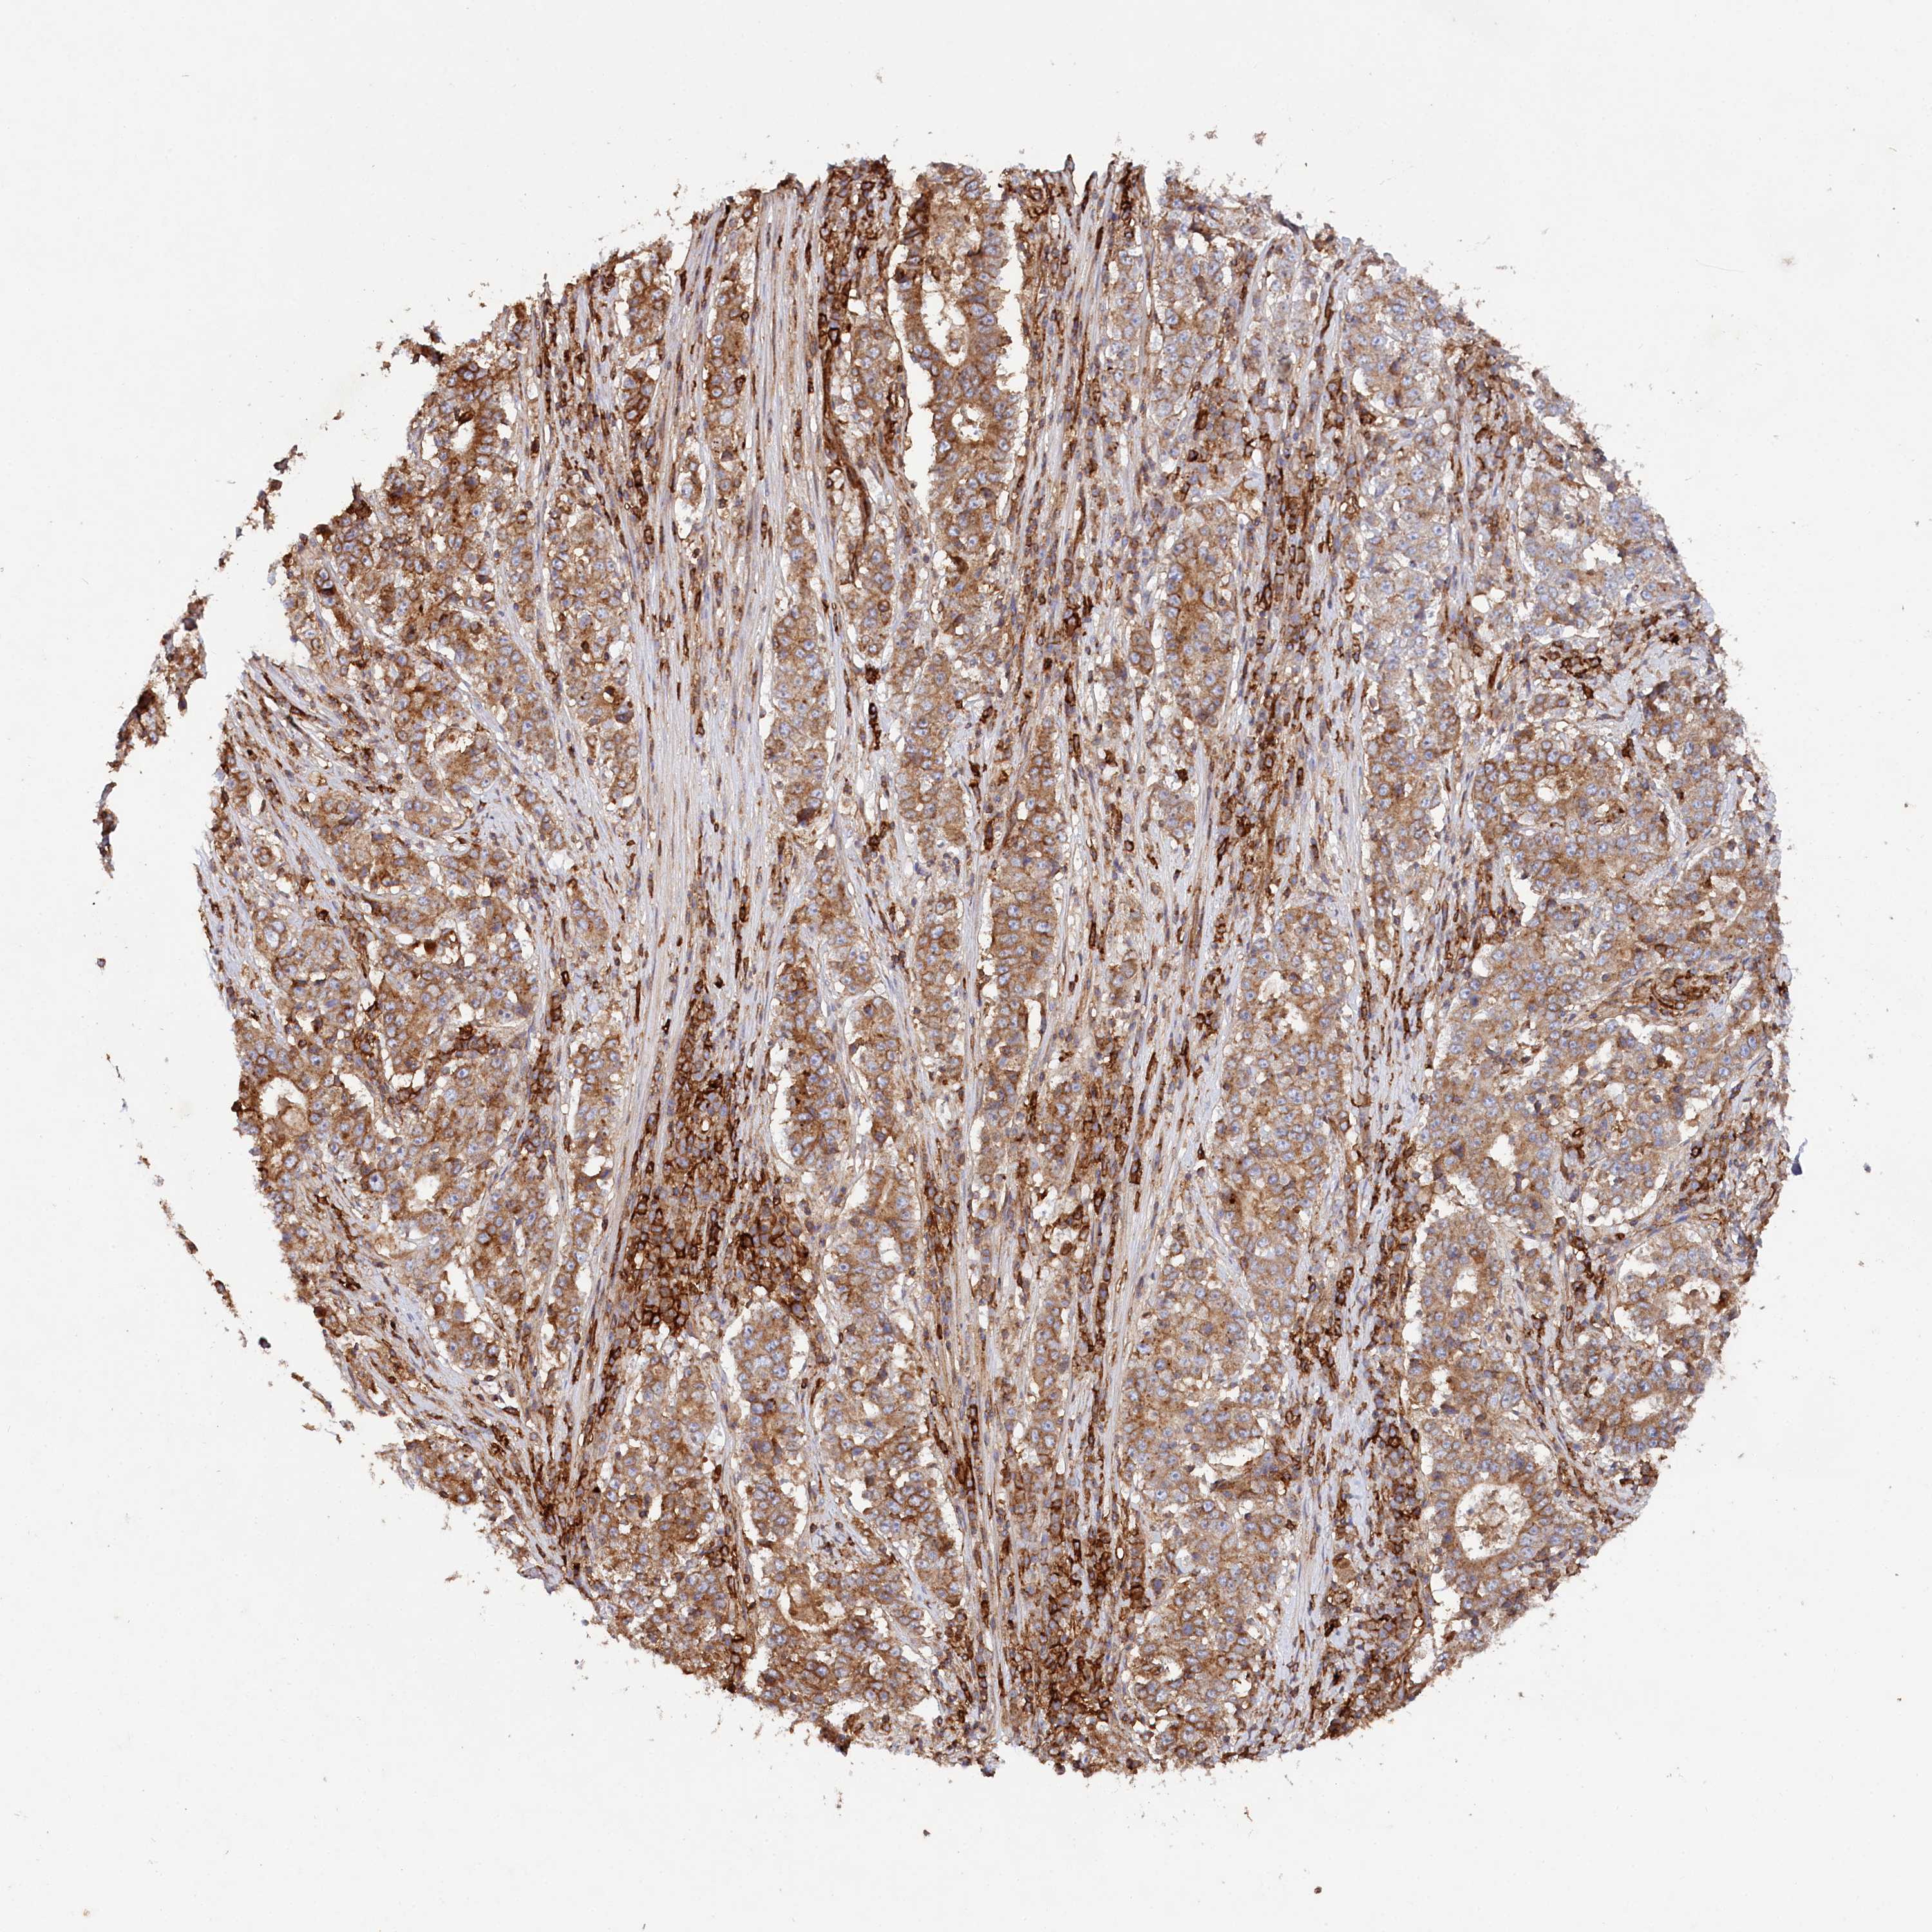

STOMACH CANCER - Protein expressioni

A mouse-over function shows sample information and annotation data. Click on an image to view it in a full screen mode. Samples can be filtered based on level of antibody staining by selecting one or several of the following categories: high, medium, low and not detected. The assay and annotation is described here.

Note that samples used for immunohistochemistry by the Human Protein Atlas do not correspond to samples in the TCGA dataset.

Antibody stainingi

Antibody staining in the annotated cell types in the current human tissue is reported as not detected, low, medium, or high, based on conventional immunohistochemistry profiling in selected tissues. This score is based on the combination of the staining intensity and fraction of stained cells.

Each image is clickable and will lead to virtual microscopy that enables deeper exploration of all samples and also displays staining intensity scores, fraction scores and subcellular localization as well as patient and tissue information for each sample.

Antibody HPA038723

Staining

High

Medium

Low

Not detected

Intensity

Strong

Moderate

Weak

Negative

Quantity

>75%

75%-25%

<25%

None

Location

Nuclear

Cytoplasmic/membranous

Cytoplasmic/membranous,nuclear

Adenocarcinoma, NOS

Adenocarcinoma, High grade